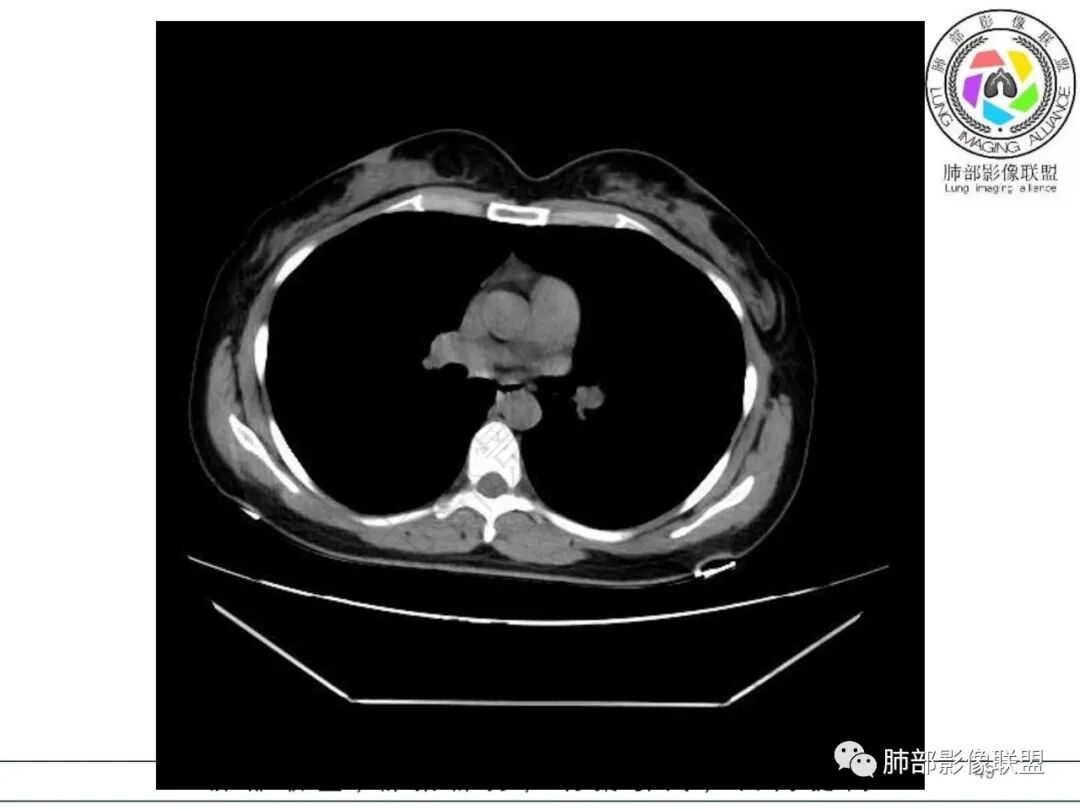

右肺下叶局限性实变影伴晕征。

女,34,畏寒、发热3天,伴纳差、恶心、呕吐。血像不高,ESR、CRP增高。胸部CT:右肺下叶局限斑片影,边缘模糊,内可见支气管穿行,个别层面融冰?肺动脉貌似增粗,考虑不典型病原体感染?肺梗?鉴别淋巴瘤等。

后、外基底段实变

周围GGO边界不清

偏密实区支气管显示欠佳,密度稍低区支气管显示,密实区边缘稍膨隆

2.影像特征:右肺下叶局限性实变影伴晕征,边界不清,内部支气管尚通畅,实变区密实区边缘稍膨隆。符合炎性病灶特征。